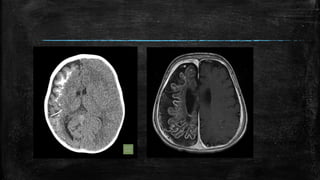

• #75 Reversal sign. Axial noncontrast CT scan of the brain in a child with severe head injury shows low attenuation of the cerebral hemispheres with complete loss of gray matter–white matter differentiation, small temporal horns, and effacement of the basal cisterns. The findings are suggestive of cerebral edema. There is relative preservation of the cerebellum (arrows) with hyperattenuation (‘white cerebellum’)

• #76 Hyperdense MCA sign. Noncontrast axial CT scans (A, B) of the brain in a patient with sudden-onset right hemiparesis show hyperattenuation of the left middle cerebral artery (arrows). This is suggestive of occlusion of the artery. This is one of the signs of acute stroke but does not necessarily represent infarction